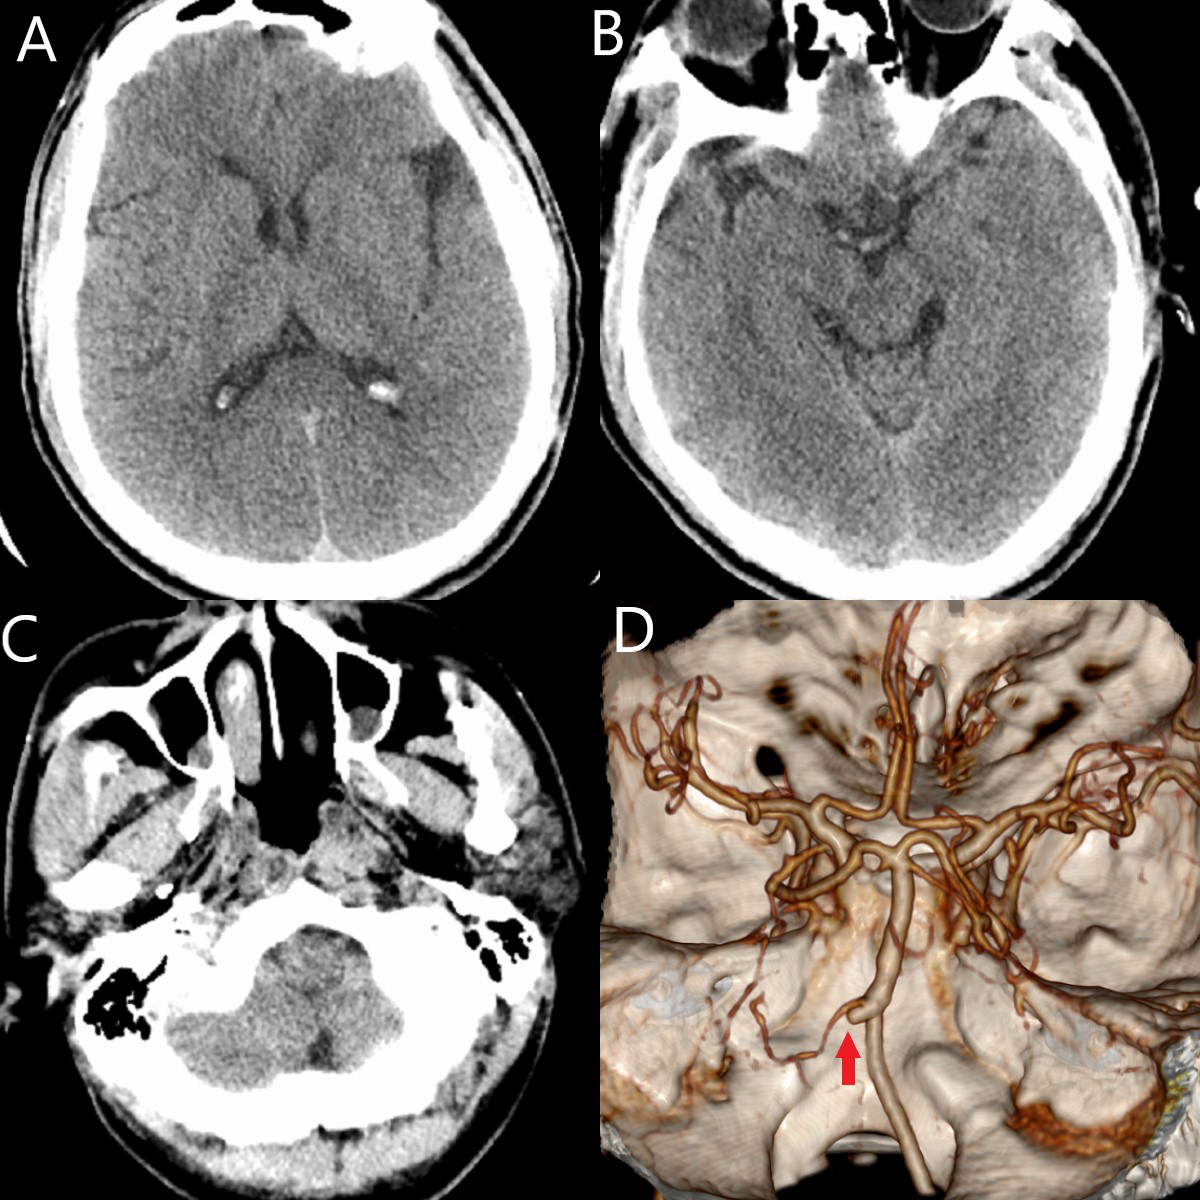

患者9小时前在工厂上班时突发头晕,恶心,伴呕吐,随即出现四肢无力,当时无摔倒。立即回家卧床休息,但头晕及无力症状无缓解。家属发现后,送当地医院就诊,当地医院CTA提示左侧椎动脉闭塞,考虑“脑梗”,予以静脉溶栓治疗。溶栓后患者头晕及肢体无力症状有所缓解。为求进一步诊治,转浙医二院急诊。浙医二院急诊头颅CTP未见明显急性低灌注征象。头颅CTA示左侧椎动脉闭塞(图1)。

图1.入院时急诊头颅CTP+CTA。A/B/C:颅内未见明显异常;D:CTA提示左侧椎动脉闭塞,重建可见左侧椎动脉残端(↑)。